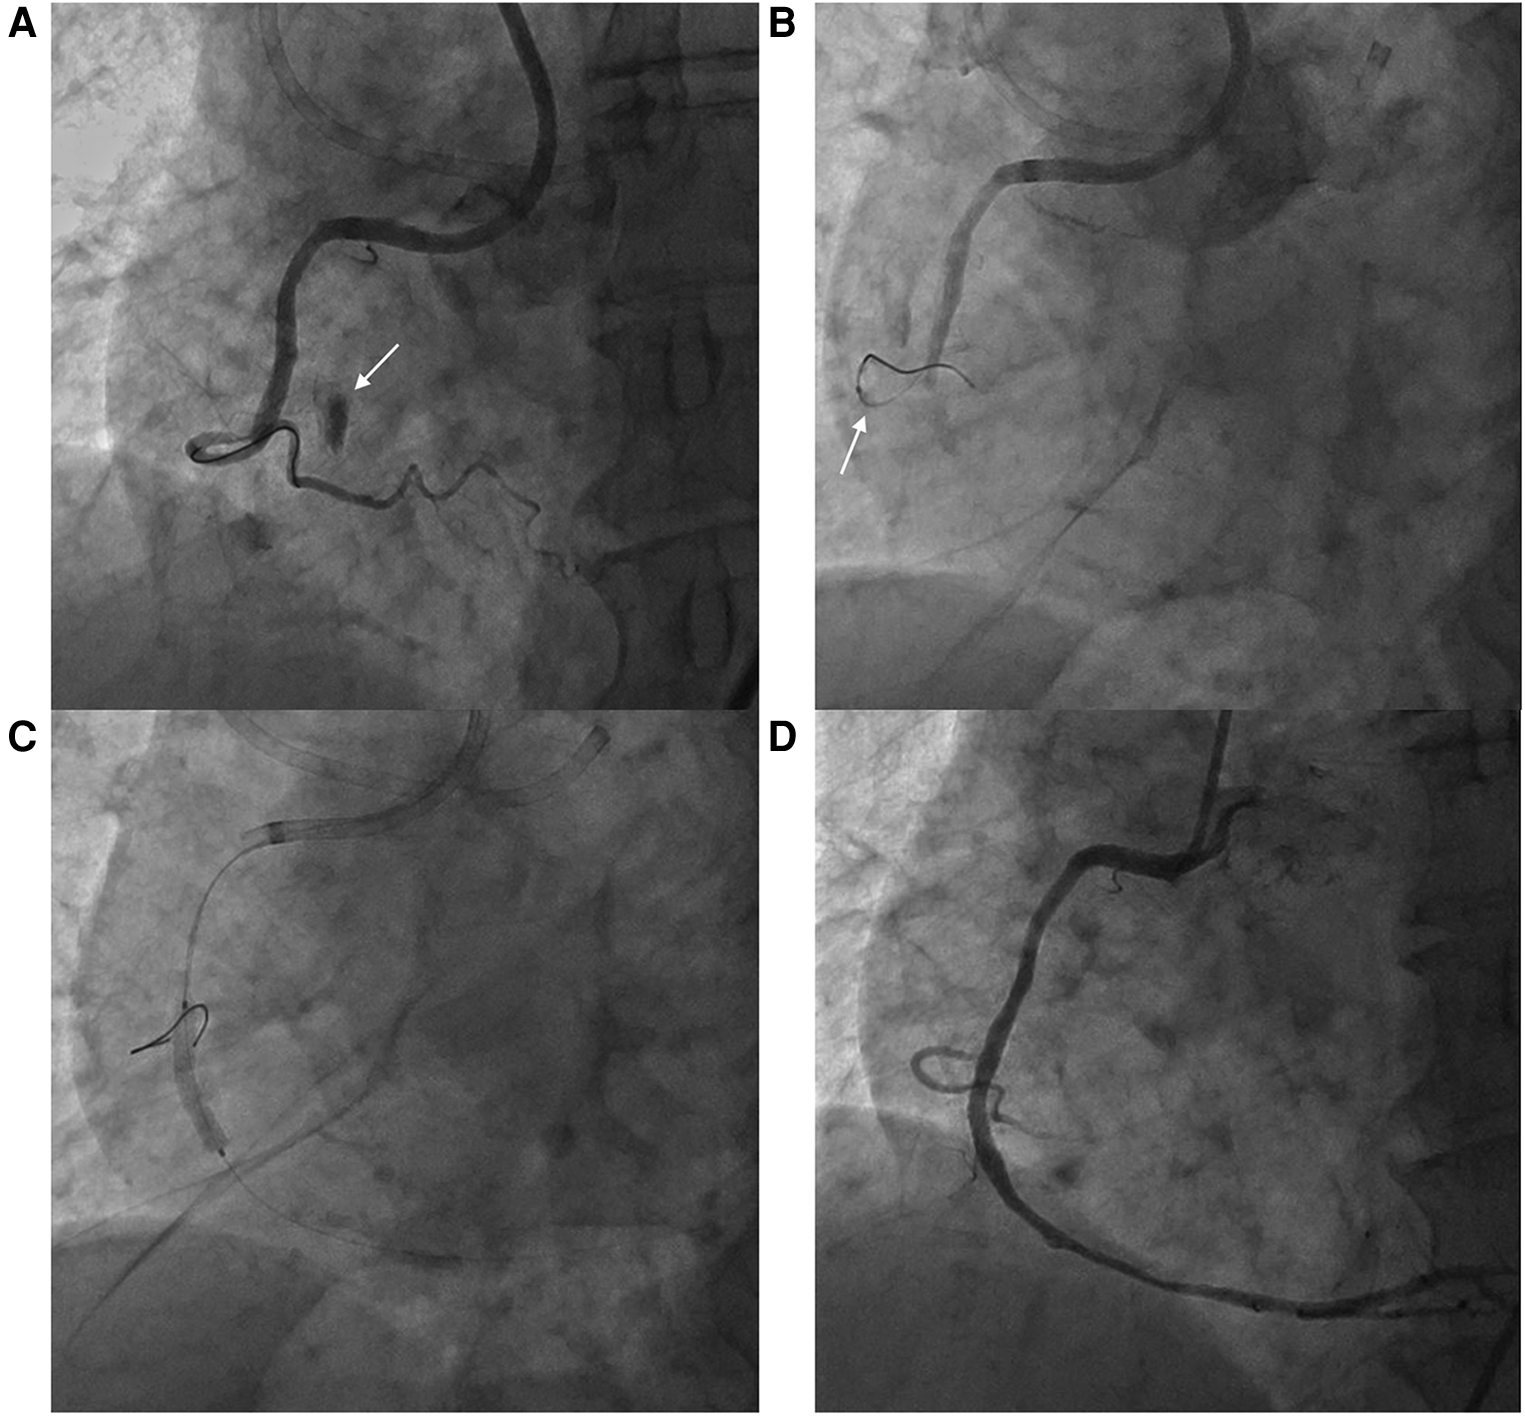

Figure 1

Right ventricular branch perforation during right coronary artery percutaneous coronary intervention. (A) Ellis classification type II microchannel perforation during right ventricular branch wiring (arrow) (B) Balloon tamponade at the perforated right ventricular branch (arrow) (C) Percutaneous coronary intervention at the right coronary artery chronic total occlusion (D) Final angiography without residual extravasation at the perforation site.

A 77-year-old man presented to the office complaining of exertional chest pain. His past history was unremarkable. An echocardiogram revealed akinesia at the RCA territory with preserved left ventricular ejection fraction (LVEF) and no pericardial effusion. The patient was admitted for further evaluation, and coronary angiography (CAG) revealed diffuse three-vessel disease, with a right coronary artery (RCA) chronic total occlusion (CTO) with thrombolysis in myocardial infarction (TIMI) grade 0 flow and collateral flow from septal branches. PCI at the RCA CTO lesion was complicated by Ellis classification type II microchannel perforation during right ventricular (RV) branch wiring proximal to the lesion for additional support during CTO wiring (Figure 1). After prolonged balloon inflation at the RCA, no continued contrast extravasation was seen, and the perforation was thought to have resolved. CTO PCI was completed without any further complications, and the patient remained stable throughout the procedure.